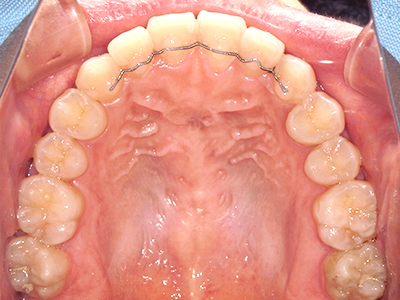

ないき歯科クリニックでは、上あごの成長不足を補い、鼻呼吸を獲得しつつ歯列を整え、将来のお口をより健康な状態にすることをゴールに定める矯正治療をおこなっています。

【4】矯正治療

矯正装置を装着し、調整しながら少しずつ歯を移動させ、歯並びを整えていきます。